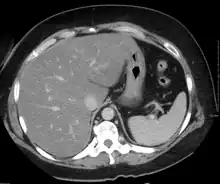

On X-ray computed tomography (CT), the increased fat component will decrease the density of the liver tissue, making the image less bright. Typically the density of the spleen and liver are roughly equivalent. In steatosis, there is a difference between the density and brightness of the two organs, with the liver appearing darker.[12] On ultrasound, fat is more echogenic (capable of reflecting sound waves). The combination of liver steatosis being dark on CT and bright on ultrasound is sometimes known as the flip flop sign.

On abdominal ultrasonography, steatosis is seen as a hyperechoic liver as compared to the normal kidney.